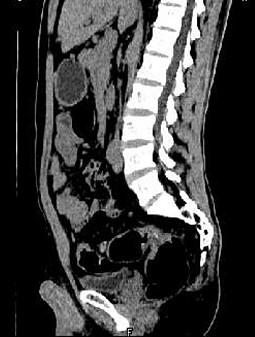

问题 女,51岁,腹胀、腹痛、进行性消瘦,影像检查如下图,最佳诊断是 ( )

选项 A、乙状结肠淋巴瘤 B、乙状结肠息肉 C、乙状结肠结核 D、乙状结肠癌 E、乙状结肠crohn病

答案 D